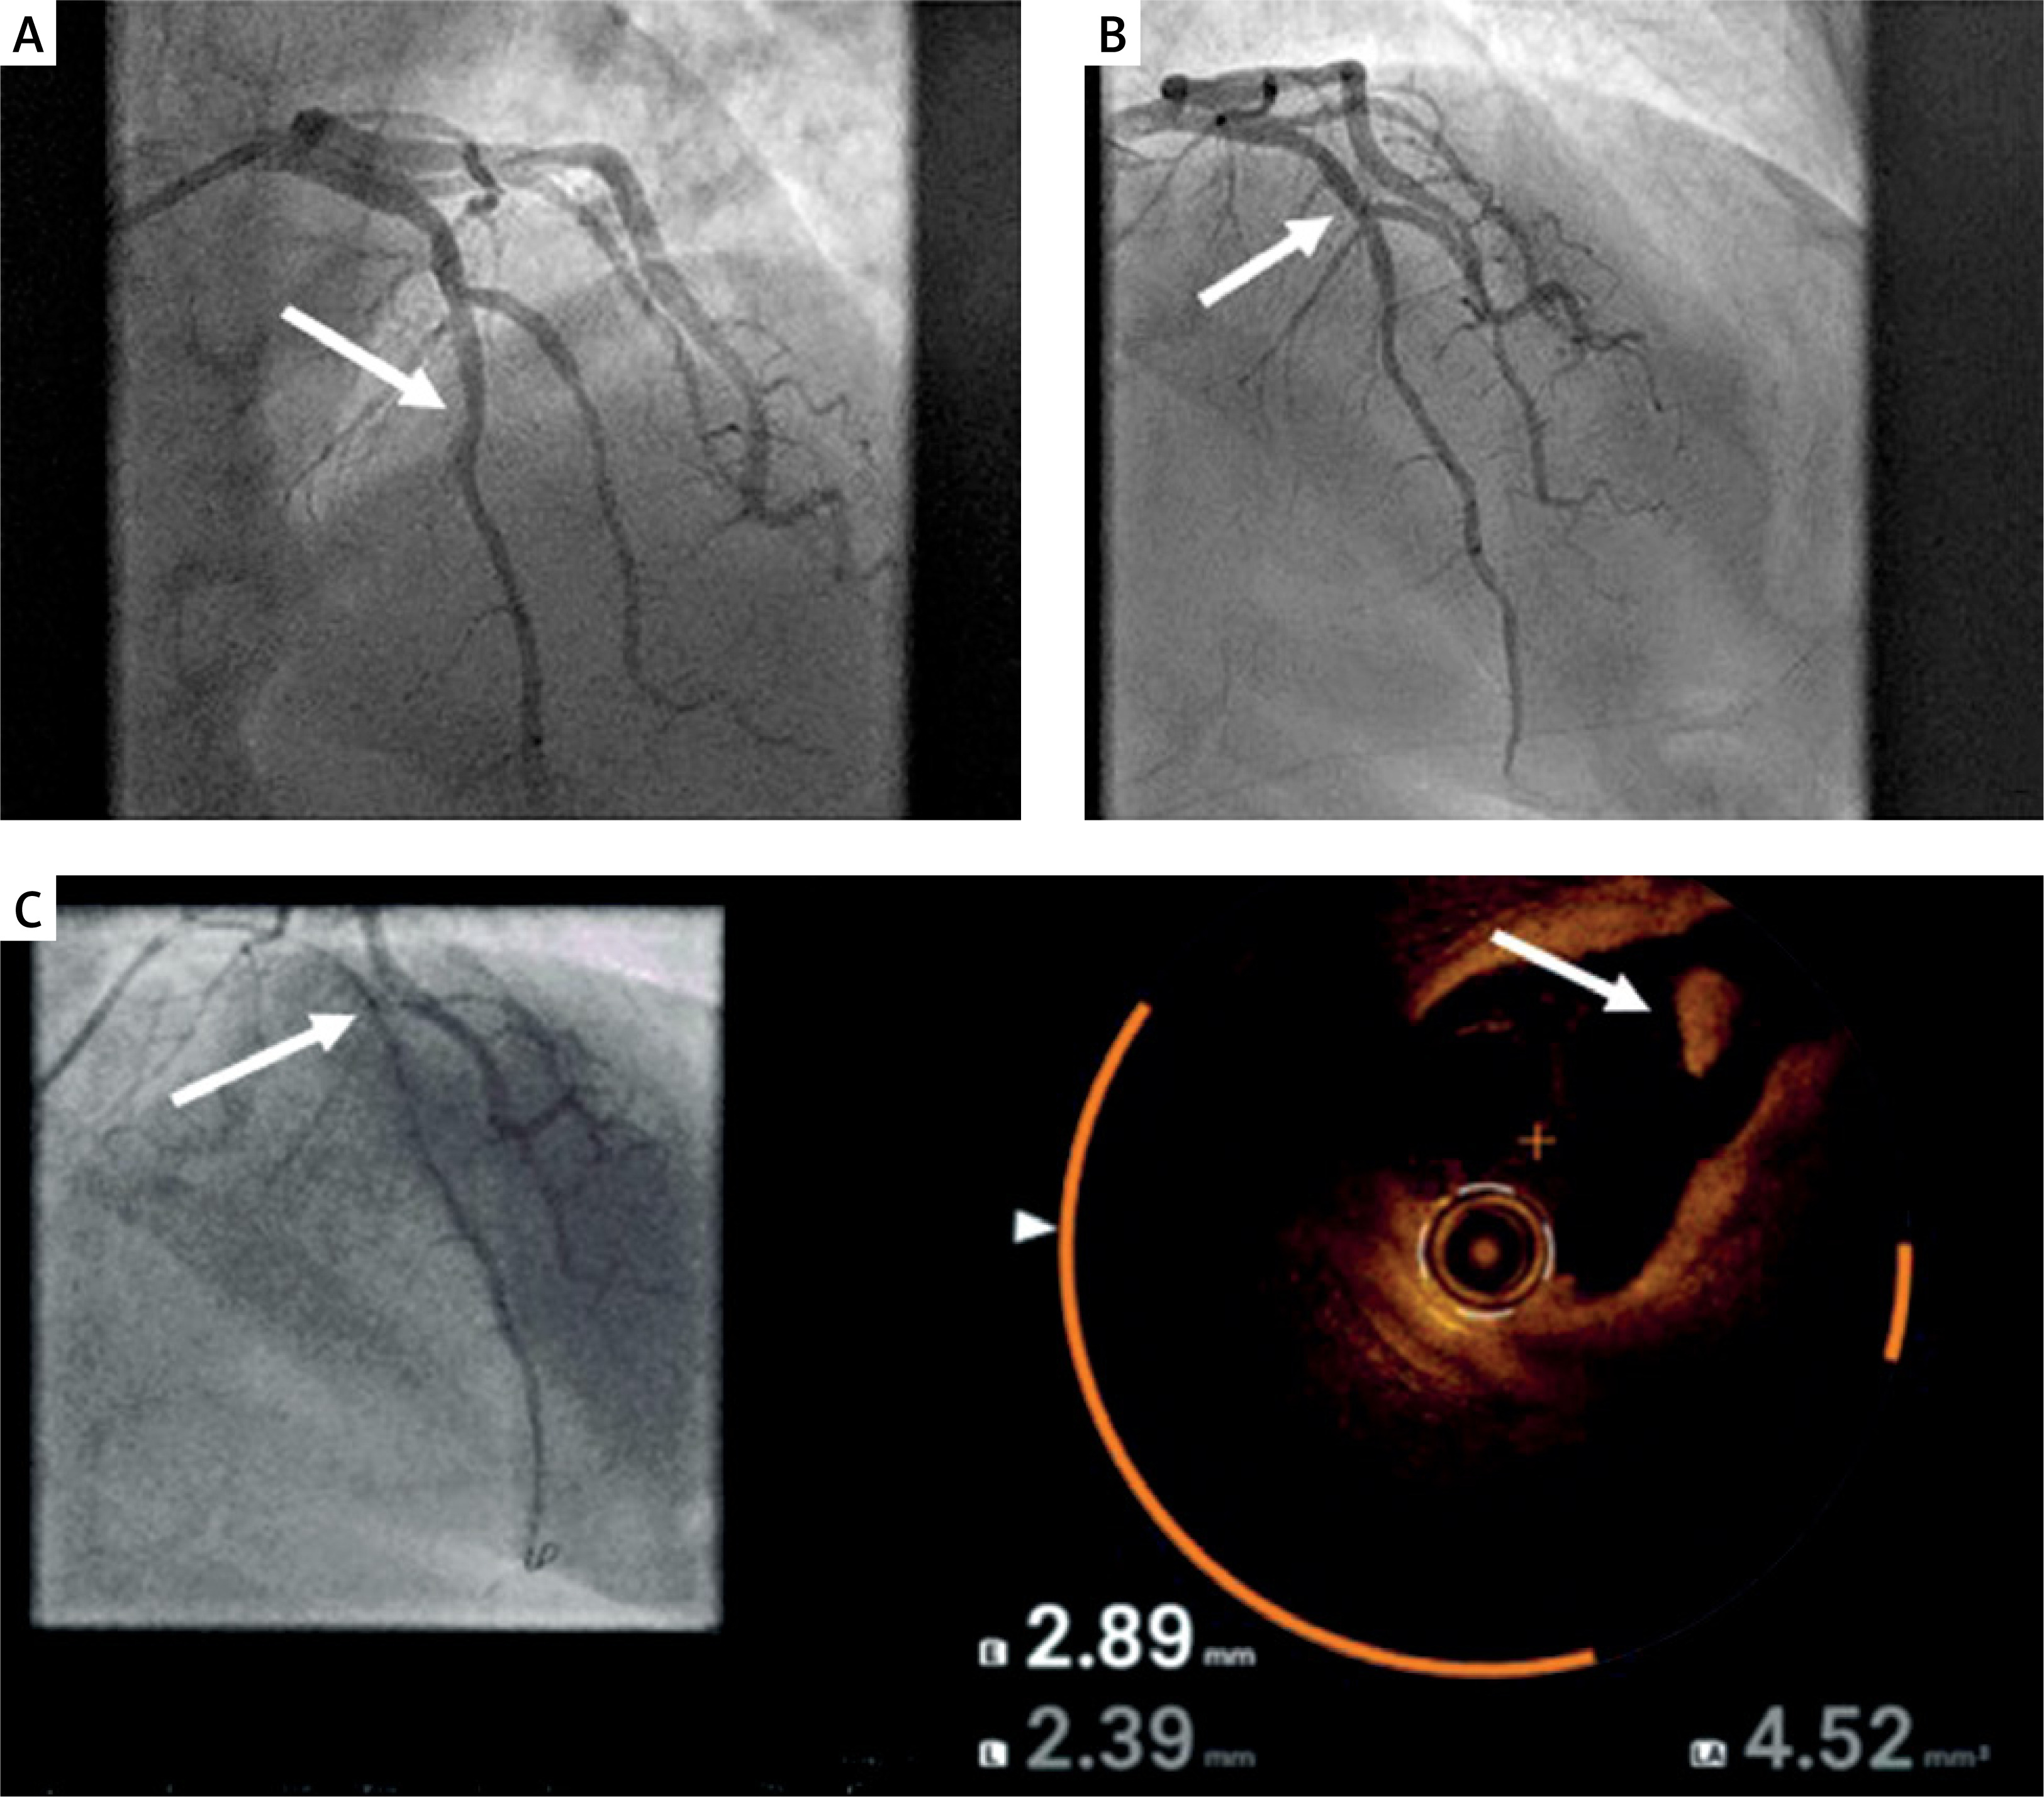

Optical coherence tomography (OCT)-guided percutaneous coronary intervention (PCI), in comparison with angiography-guided PCI, helps to establish the diagnosis, define the treatment plan, and improve outcomes. However, its widespread adoption is still limited [1]. We present an OCT image in a patient after out-of-hospital cardiac arrest (OHCA), which changed the treatment course and allowed the deferred PCI to be conducted. A 61-year-old female patient with a history of atrial fibrillation (AF), ischemic stroke, type 2 diabetes and hypercholesterolemia was admitted because of OHCA due to ventricular fibrillation. After a successful resuscitation, electrocardiography showed evolution of the anterior ST-elevation myocardial infarction. Coronary angiography revealed normal coronary arteries and a large thrombus in the left anterior descending (LAD) artery with TIMI 3 flow (Figure 1 A). Considering chest pain resolution in the catheterization laboratory with no possibility to identify the place of plaque rupture and the risk of no-reflow associated with ad hoc PCI due to distal embolization, the decision to defer PCI was made. Eptifibatide was administered periprocedurally, and the patient was discharged home on triple antithrombotic therapy (acetylsalicylic acid, clopidogrel, rivaroxaban). After 2 weeks, the follow-up angiogram showed a normal LAD with no signs of plaque or thrombus (Figure 1 B). However, the OCT showed a clear plaque rupture in the mid LAD, defining the diagnosis and prompting PCI with a short stent (Figure 1 C). Since currently there are no clear guidelines regarding the treatment of patients with a large thrombus burden, the treatment options range from direct stenting with or without distal protection devices to deferred PCI or no PCI at all [2]. The risks associated with immediate PCI in this scenario include no reflow and suboptimal stent choice (too long or too small). Deferred PCI using stents or drug-coated balloons seems to improve outcomes compared to immediate stenting, provided that the patient is stable and there is TIMI 2-3 in the infarct-related artery [3, 4]. In the absence of significant stenosis in the infarct-related artery, patient management without PCI also appears safe [5]. In a prospective observational study including acute coronary syndrome (ACS) patients with a large thrombus burden who had undergone coronary angiography with OCT, 38% of patients were treated stent-free, all with favorable outcomes [4]. The optimal time for follow-up angiography has also not been defined and ranges from 1 day to 1 month. However, the later it is performed after the index event, the less stenting is required (preferably more than 7 days) [3–5]. Since angiography underestimates the thrombus burden, intravascular imaging is crucial to guide treatment in this complex scenario. It enables precise assessment of lesion morphology (plaque rupture vs. erosion vs. calcified nodule), length, and diameter, thereby avoiding PCI with implantation of too long or too short stents and reducing the risk of recurrent thrombotic events [3–5]. In our case, OCT provided information that could not be obtained with coronary angiography, helping to establish the diagnosis of coronary plaque rupture as a cause of OHCA and guide further management.

Figure 1

A – Coronary angiography showing thrombus in left anterior descending coronary artery (LAD; white arrow); B – Follow-up coronary angiography after 2 weeks of triple antithrombotic therapy with no signs of plaque or thrombus in LAD; C – Coregistration of angiography and optical coherence tomography showing plaque rupture in the mid LAD segment (white arrow)